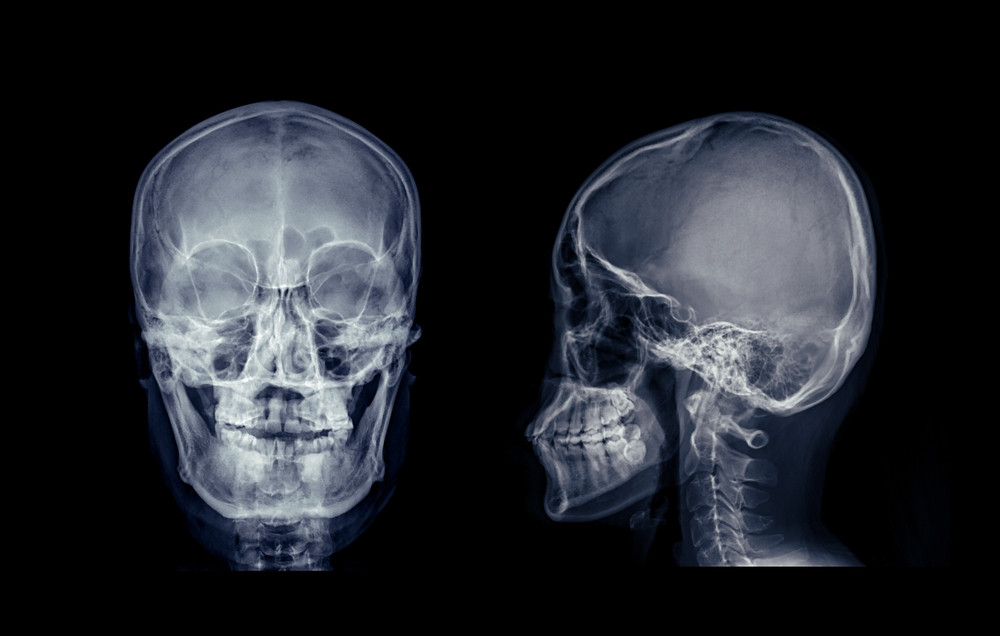

Imagerie médicale

Le diagnostic repose sur des examens précis :

Scanner du rocher : identifie la fracture et ses orientations

IRM : évalue l’atteinte des structures nerveuses et de l’oreille interne